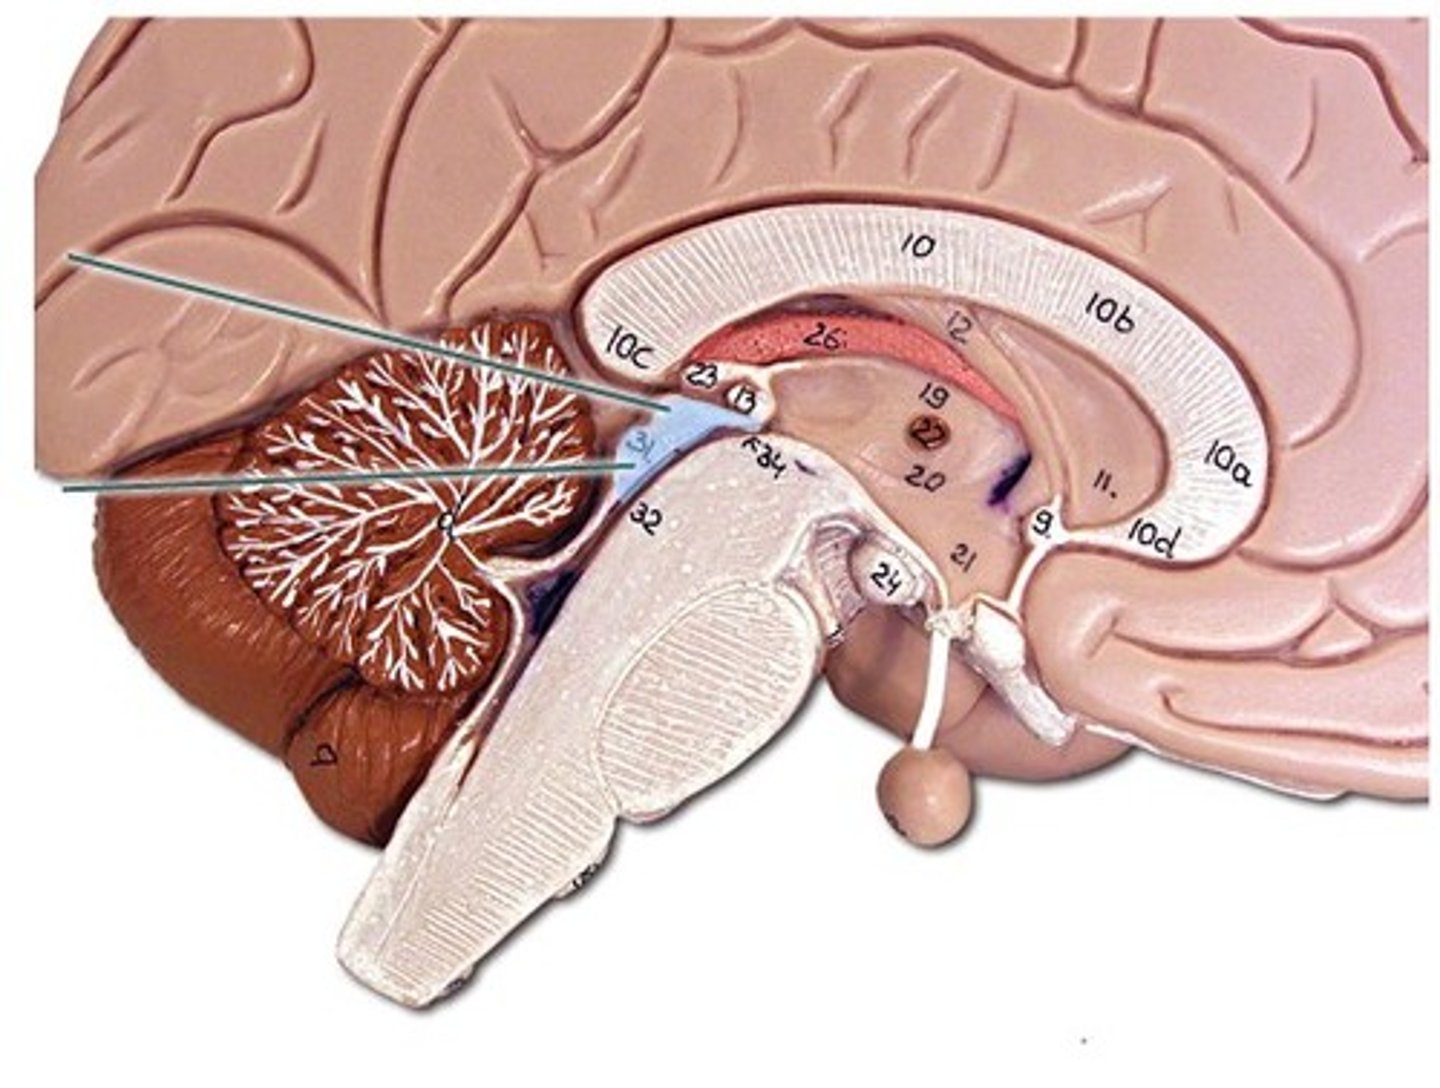

brainstem

cerebellum

cerebrum

hypothalamus

medulla oblongata

lateral ventricles

midbrain

pons

thalamus

arachnoid villus

corpus callosum

frontal lobe

fornix

cerebral aqueduct (brainstem)

corpora quadrigemina (brainstem)

fourth ventricle

hypophysis (pituitary gland)

infundibulum

intermediate mass of thalamus

pineal gland

choroid plexus (of ventricles)

third ventricle